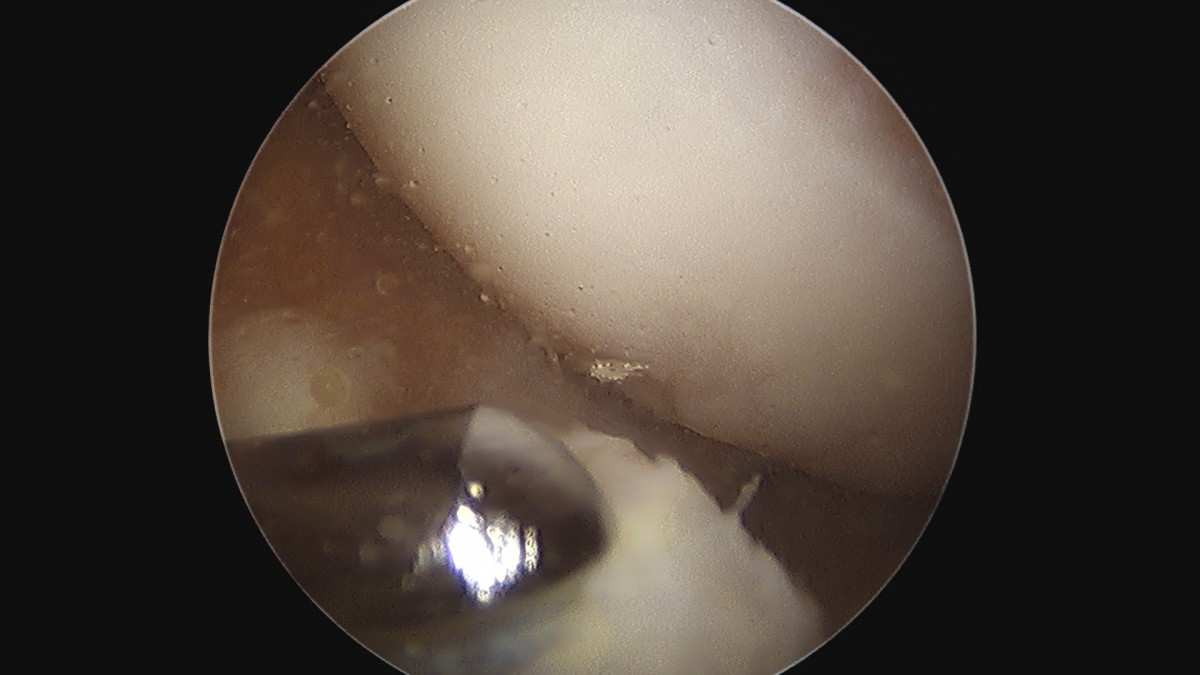

이재상원장님 무릎 반월상 연골판 절제술 안경O 환자

작성자 최고관리자 댓글 0건 조회 374회 작성일 25-09-16 15:58